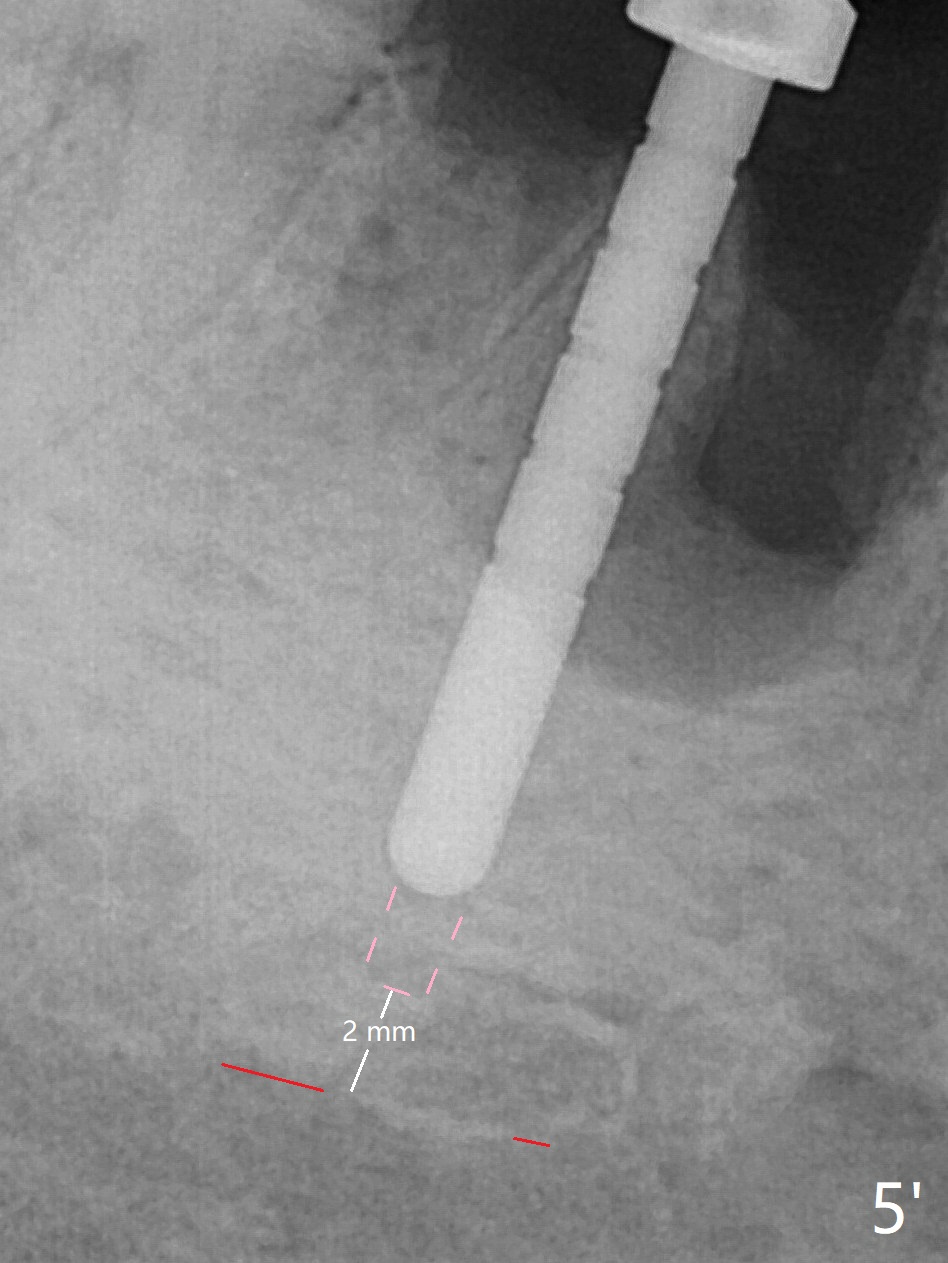

Preop oral Amoxicillin seems to be associated with reduction in the buccal and lingual (Fig.3 arrow) fistulae at #30, but there is mesiobuccal swelling (Fig.1 *) with 7 mm pocket (Fig.2). Osteotomy is initiated in the middle of the septum (Fig.3-5 S). As the osteotomy increases, it shifts mesially (Fig.6 arrow). Guided surgery is able to reduce shifting. A 5x13 mm implant is not seated completely (Fig.7) apparently due to osteotomy shifting. After removal of the bone from the osteotomy distally, the implant remains unseated with lower torque value (Fig.8). Following reuse of the 4.3 mm drill deeper by 1-2 mm, the implant is seated to a satisfactory depth (Fig.9 with increase in torque to 50 Ncm) with placement of Vera Graft (*) and a 7.5x4(3) mm abutment. After a second round of allograft placement (Fig.10 *), the implant is found to be 4 mm from the IAC. At the later stage of osteotomy, the coronal end of the septum is destroyed with loss of osteotomy depth landmark. It is apparent that the soft tissue landmark may be more reliable. The implant threads appear to be covered by the bone graft 3.5 months postop (Fig.11). The abutment is changed to 6.5x5(3) mm one before impression with minor margin prep. The bone density seems to increase 5 months postop, i.e., immediately post cementation (Fig.12) and 10 months postop (5 months post cementation (after retightening abutment), Fig.13 (*)). Periimplantitis develops mesiobuccally, consistent with bone loss 1 year 7 months post cementation (Fig.14 *); the implant seems to have been buccally placed. Bone graft is necessary with PRF or GEM21S if the vein is small and 6-month membrane with a hole around a 7.5x4(4) cemented abutment for easy wound closure. Take 5x5 CM CBCT to determine which wall has defect, buccal or lingual. Check mesial contact. If so, remove the crown, reseat the abutment (possible incomplete seating) and re-impress after bone graft.